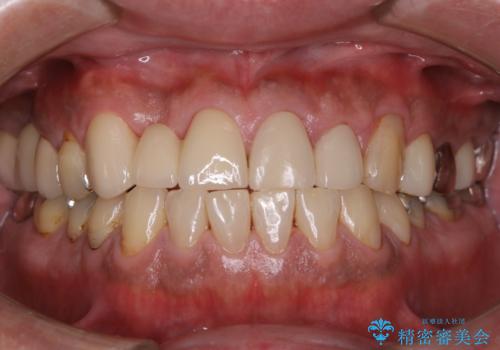

タバコによるヤニをPMTCで除去